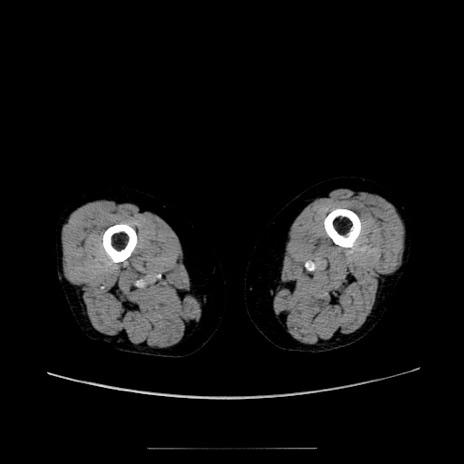

【症例】70歳代女性

【主訴】お腹が張る

【現病歴】1週間くらい前から腹部膨満の自覚あり。昨日夜から増悪したため、本日救急外来受診。

【身体所見】意識清明、BT 36.5℃、BP 165/106mmHg、HR 80bpm、SpO2 98%、腹部:膨満、軟、自発痛・圧痛なし、触診にて不快感あり、腸蠕動音:減弱

【データ】WBC 12600、CRP 1.04